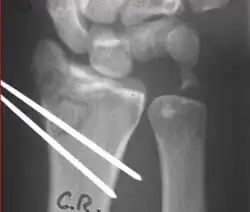

Surgical options have been shown to be successful in patients with unstable extra-articular or minimal articular distal radius fractures. These options include percutaneous pinning, external fixation, and ORIF using plating. Patients with low functional demand of their wrists can be treated successfully with nonsurgical management; however, in more active and fit patients with fractures that are reducible by closed means, nonbridging external fixation is preferred, as it has less serious complications when compared to other surgical options.[5] The most common complication associated with nonbridging external fixation is pin tract infection, which can be managed with antibiotics and frequent dressing changes, and rarely results in reoperation.[5] The external fixator is placed for 5 to 6 weeks and can be removed in an outpatient setting.[5]

These fractures, although less common, often require surgery in active, healthy patients to address displacement of both the joint and the metaphysis. The two mainstays of treatment are bridging external fixation or ORIF. If reduction can be achieved by closed/percutaneous reduction, then open reduction can generally be avoided. Percutaneous pinning is preferred to plating due to similar clinical and radiological outcomes, as well as lower costs, when compared to plating, despite increased risk of superficial infections.[24] Level of joint restoration, as opposed to surgical technique, has been found to be a better indicator of functional outcomes.[5]